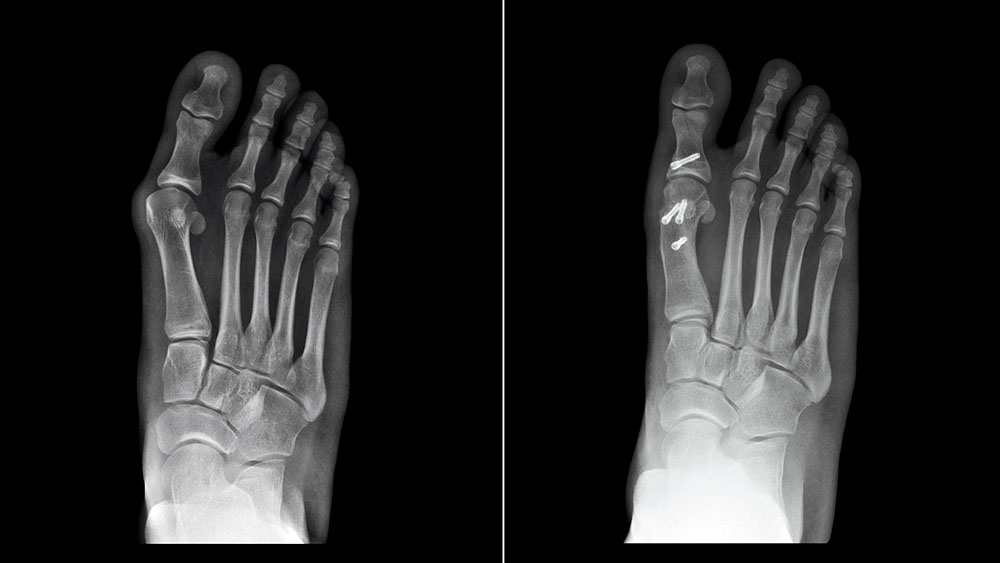

Bunionectomies

We treat bunions with both non-surgical options like custom orthotics and therapy—and advanced surgical techniques when needed to restore comfort and alignment.

Hallux Valgus

This common toe deformity is treated through a personalized plan that may include orthotics, footwear changes, or corrective surgery, depending on your needs.